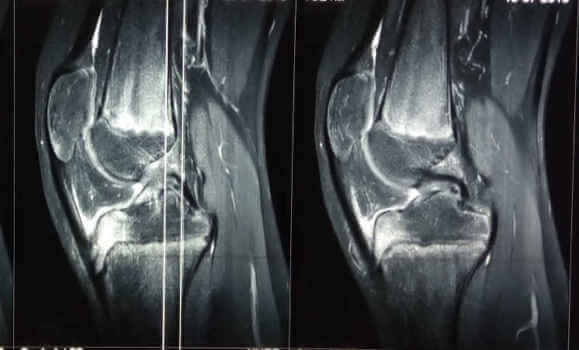

Η ακτινολογική εικόνα με την εικόνα του κατακερματισμού της επίφυσης του κνημιαίου κυρτώματος συνδυάζεται με την κλινική εικόνα για την διάγνωση της νόσου. Ο έλεγχος με μαγνητική τομογραφία αναδεικνύει το οστικό οίδημα της επίφυσης του κνημιαίου κυρτώματος.

Εικόνα Ακτινολογική εικόνα με κατακερματισμό και οριακή απόσπαση του κνημιαίου κυρτώματος. Η μαγνητική τομογραφία αναδεικνύει το οίδημα της επίφυσης, με φυσιολογική εικόνα της επιφυσιακής πλάκας.